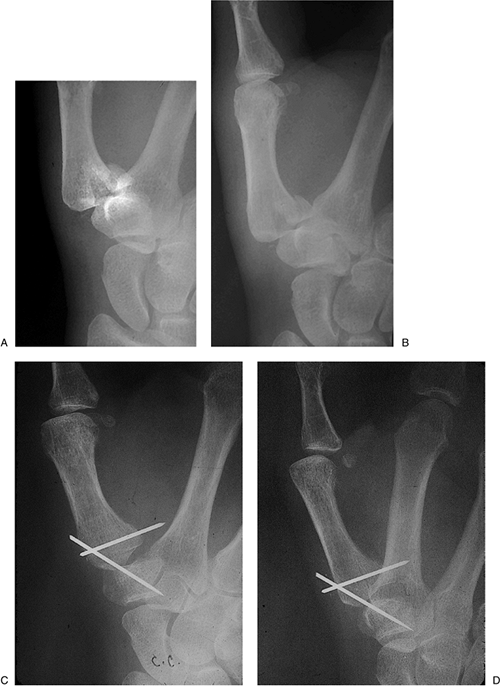

Figure 9-20 X-ray appearance of Bennett’s fracture with K-wire fixation. A, B. Prereduction appearance. C, D.

Note the anatomic reduction and K-wire fixation of the fracture

fragment, and a second transarticular K-wire across the CMC joint. Question

to the reader: What would you have done differently in terms of the cut

off ends of the K-wires? Answer: A 90-degree bend prior to cutting off

the K-wires would have prevented migration of the ends of the pins

beneath the dorsal cortex of the metacarpal and made pin removal at 6

weeks a less complex procedure. -

Figure 9-20 demonstrates the x-ray appearance of a Bennett’s fracture and its reduction and fixation with K-wires.